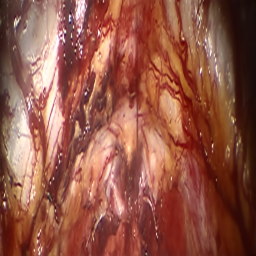

Refer to caption (a) Input Refer to caption (b) DIACMPN Refer to caption (c) Desmoke-LAP Refer to caption (d) PFAN Refer to caption (e) MITNET Refer to caption (f) Salazar Refer to caption (g) Dehamer Refer to caption (h) Ours Refer to caption (i) Target

Figure 2: Comparison of different methods on the DesmokeData dataset.

IV-C2 Qualitative Analysis

Figures 3 and 2 provide a visual comparison of the desmoking results on challenging images from the test sets. The visual results corroborate our quantitative findings. DCP not only fails to remove the dense smoke but also introduces severe color distortion. CNN-based methods like FFA-Net and MSBDN successfully remove a large portion of the smoke but tend to either leave behind a thin layer of residual haze or over-smooth the image, losing critical textural details of the tissue and surgical instruments. The Transformer-based methods, DehazeFormer and PFAN, produce significantly better results by restoring more details. However, they can sometimes struggle with non-uniform smoke distribution, resulting in regions with unnatural brightness or minor artifacts.

In stark contrast, our RGA-Net generates visually superior results that are remarkably close to the ground-truth images. It effectively removes even the densest plumes of smoke while simultaneously preserving fine-grained details, such as blood vessels, tissue textures, and reflections on surgical tools. Furthermore, the color and illumination of the restored scene appear more natural and consistent, which is a direct benefit of our model’s ability to handle both local and global features through its hybrid attention and cross-gating mechanisms. This enhanced visual clarity is crucial for improving the surgeon-robot interface in real-world clinical applications.